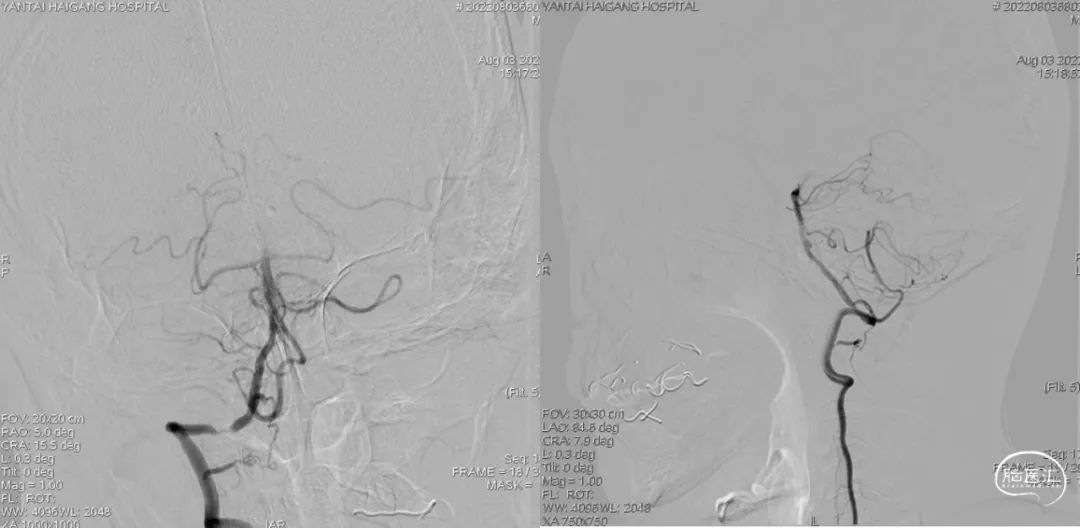

左椎动脉+左颈动脉造影:

右椎动脉造影:

右颈动脉造影:

右椎动脉动脉正侧位:

病变情况分析:右桡动脉穿刺,置6F桡动脉鞘管,5F多功能导管在泥鳅导丝辅助下脑血管造影提示:右椎动脉V4段重度狭窄(约90%)。